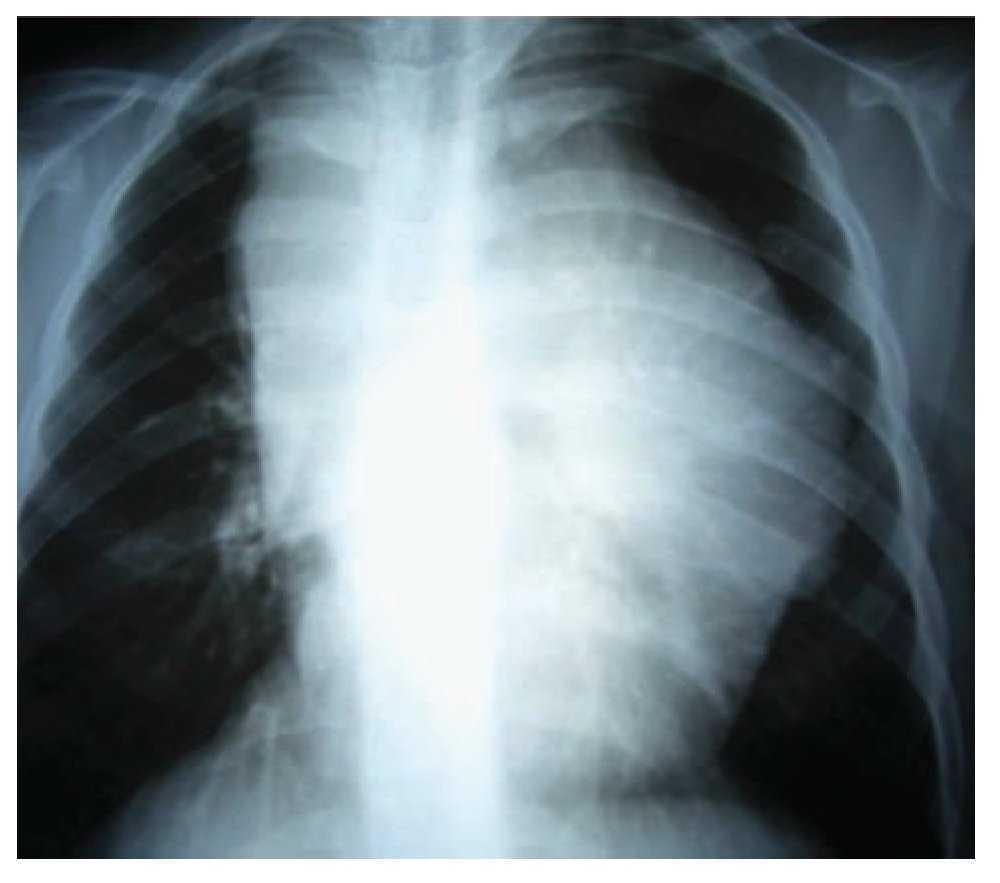

Adolescente femenino de 12 años de edad con antecedentes de cáncer materno en cinco miembros de la familia, con un cuadro de seis meses de evolución con deterioro de su estado general (astenia, adinamia, hiporexia, fiebre vespertina hasta de 380, pérdida de 8 kg de peso) y adenopatías periféricas. En la exploración física se percibe conglomerado ganglionar supraclavicular derecho e izquierdo de 5 cm por 3 cm, red venosa colateral en la cara antero-superior de hemitórax izquierdo, hipoventilación superior izquierda con matidez a la percusión; el resto de la exploración resulta negativa. Los exámenes de laboratorio fueron normales, excepto la velocidad de sedimentación globular 30 mm/60 min. La radiografía de tórax mostró una gran masa en el mediastino (Imagen 1); la tomografía axial computarizada de tórax reveló una imagen lobulada, hiperdensa hacia el parénquima pulmonar, localizada en el mediastino medio, anterior y superior, que desplazaba la silueta cardiaca hacia abajo y hacia el lado izquierdo, la cual mostraba reforzamiento leve cuando se aplicó contraste. Además, comprimía, en su porción posterior, ambos hilios sin obliterarlos; el parénquima pulmonar sin alteraciones (Imagen 2).

Imagen 2. Corte tomográfico que muestra una imagen lobulada hiperdensa en dirección del parénquima pulmonar, que se ubica en el mediastino medio, anterior y superior.